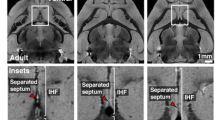

The isocortical (neocortical) SP zone is formed by the secondary expansion of CP cells between 13 and 15 PCW (Duque et al. 2016). Here, regional differences in the SP formation process are observed with Tbr1 marker between the dorsal isocortex and medial interhemispheric cortex composed of the dorsal isocortical and ventral mesocortical portion of the cingulate cortex (Fig. 7). Using Tbr1 immunohistochemistry, we observed the absence of CP delamination (secondary expansion of SP) in the archicortex (Fig. 7). Thus, our main findings reveal how to anatomically differentiate and delineate the dorsal isocortical part of the cingulate gyrus, ventral allocortical-mesocortical part of the cingulate gyrus, and the archicortex (future indusium griseum). The neocortex is characterized by the complete “second” cortical plate (Poliakov 1949) formation and consequently, complete SP formation from the deeper portions of the CP. We correlated these neuroanatomical findings with DPN marker Tbr1 (Figs. 7, 13). Remarkably, the mesocortical part of the cingulate cortex is characterized by the incomplete “second” plate formation; on the contrary, the archicortex has no “second” plate nor the SP formation (Figs. 7, 8). At 13 PCW, CC is formed in the anterior brain portions and it is seen as fibers between iSVZ and oSVZ. The tissue bridge between the two cerebral hemispheres which may correspond to the precallosal “sling” is visible only in some planes of the earliest specimen examined in our study (Shu and Richards 2001).

Subplate formation period revealed by the deep projection neuron marker Tbr1 at 13 PCW, coronal sections, anterior part. Rectangles a, b, c, and d represent the dorsal isocortex (a), medial isocortex (b) and parts of the cingulate cortex (c, d) with magnified images. SP is formed from the deep portion of the CP in the dorsal isocortex, as well as in the dorsal isocortical part of the cingulate cortex (marked with red asterisk). Incomplete SP expansion is observed in the mesocortical ventral cingulate cortex (red arrow), while the archicortical part is characterized by the absence of CP delamination-absence of SP expansion (black arrow). Black lines define the borders between complete, incomplete and absent SP expansion (CP delamination). Corpus callosum is formed, seen as callosal fibers between iSVZ and oSVZ. MZ marginal zone, CP cortical plate, SPf subplate in formation, SVZ subventricular zone, iSVZ inner SVZ, oSVZ outer SVZ, VZ ventricular zone, CC corpus callosum. Scalebar: 100 μm

Dorsal and ventral cingulate cortex characteristics (coronal sections, intermediate part—level of the hippocampus) revealed by Nissl staining (a, b, c) and Tbr1 immunohistochemistry (d, e, f, g). Coronal Nissl-stained section at 13 PCW at the level of the hippocampus (a). Magnification from the rectangle shows dorsal cingulate cortex (dorsal pattern) and prospective cingulate sulcus (red arrow) (b). Laminar architecture of neocortical dorsal cingulate cortex (c). Coronal section at 13 PCW at the level of the hippocampus shown with Tbr1 marker (d). Magnification from the rectangle (e) shows the dorsal (f) and ventral (g) portion of the cingulate cortex. Laminar architecture of the neocortical dorsal cingulate cortex (f). Laminar architecture of the mesocortical ventral cingulate cortex: wide MZ, thinner CP and no SP expansion (g). Please note that the ventral cingulate portion (g) was detached during tissue processing. MZ marginal zone, CP cortical plate, SPf subplate in formation, SVZ subventricular zone, iSVZ inner SVZ, oSVZ outer SVZ, VZ ventricular zone. Scalebar: 100 μm